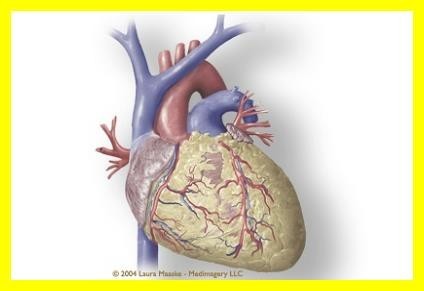

오늘은 정말 많은 분들이 놓치기 쉬운 **치명적인 심장 질환, ‘심근경색’**에 대해 이야기해보려 합니다.심근경색은 말 그대로 심장 근육이 괴사하는 질환으로, 골든타임을 놓치면 생명을 잃을 수 있는 응급상황입니다.